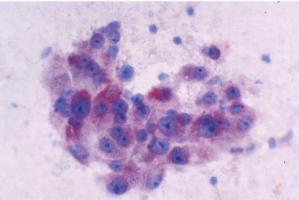

Actualité publiée le 03/11/2021De la STÉATOSE HÉPATIQUE à la stéatohépatite non alcoolique, quels mécanismes ?